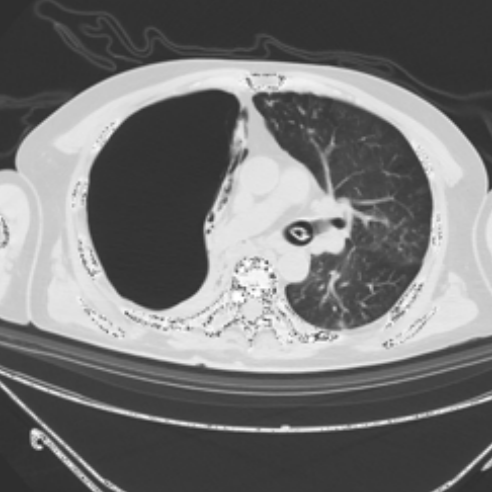

医生怀疑肺大泡破裂导致气胸;但是,由于血流动力学和呼吸状态稳定,未置入胸腔引流管

。 胸部 CT显示右肺肺不张,少量胸腔积液

(图4)。

图4. CT显示右肺肺不张